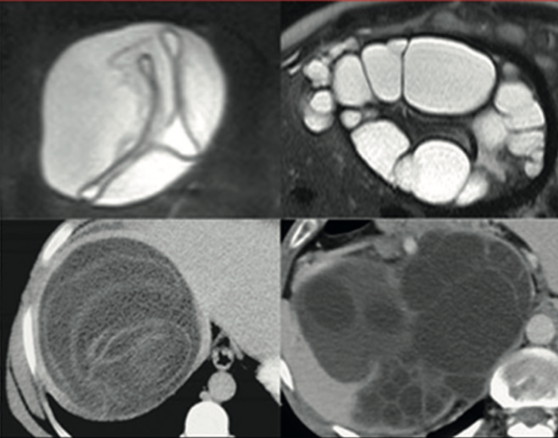

Manuel Antonio Grez ibàñez, Luis Gerardo Antequera Velásquez

|

|

|